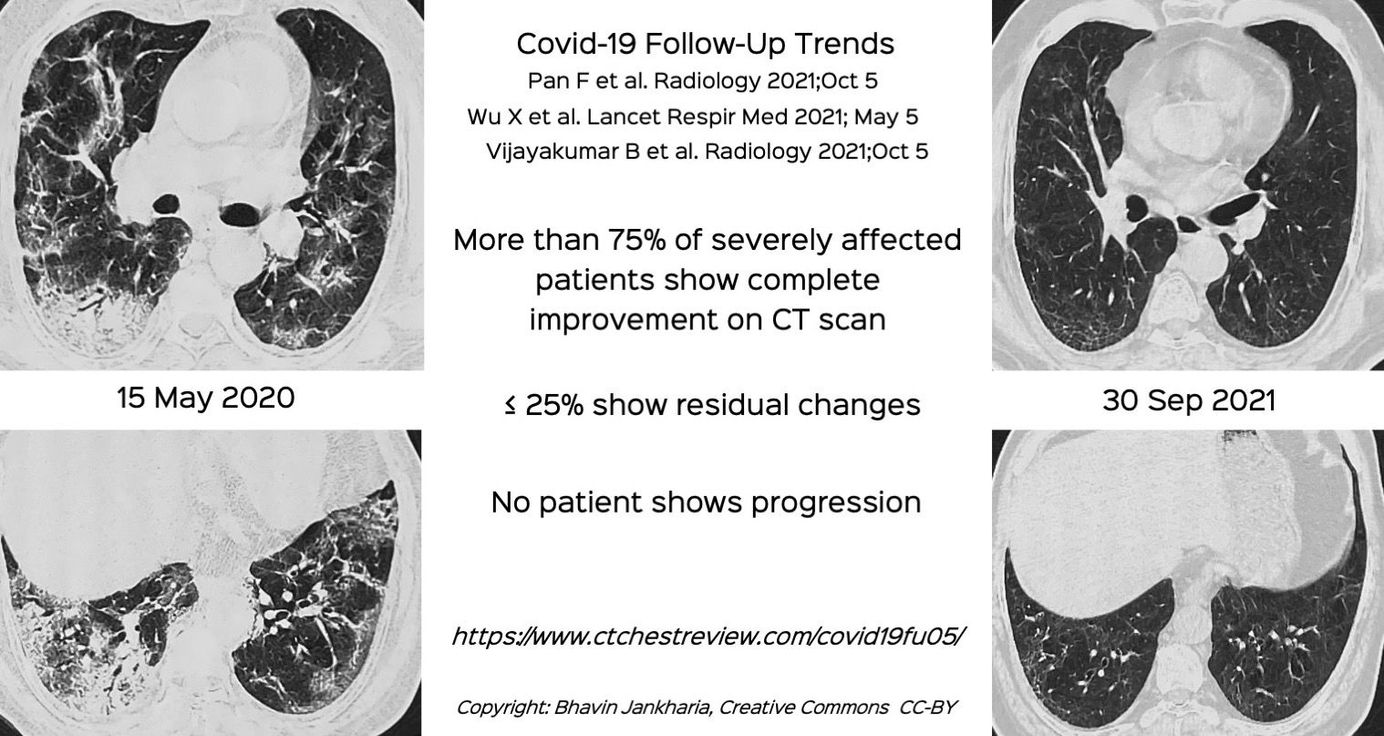

Case 32: Covid-19 - 16.5 Months Follow-Up, Review of Follow-Up Articles and Summary of General Trends Paid Members Public

16 1/2 months follow-up of Covid-19 and other learnings